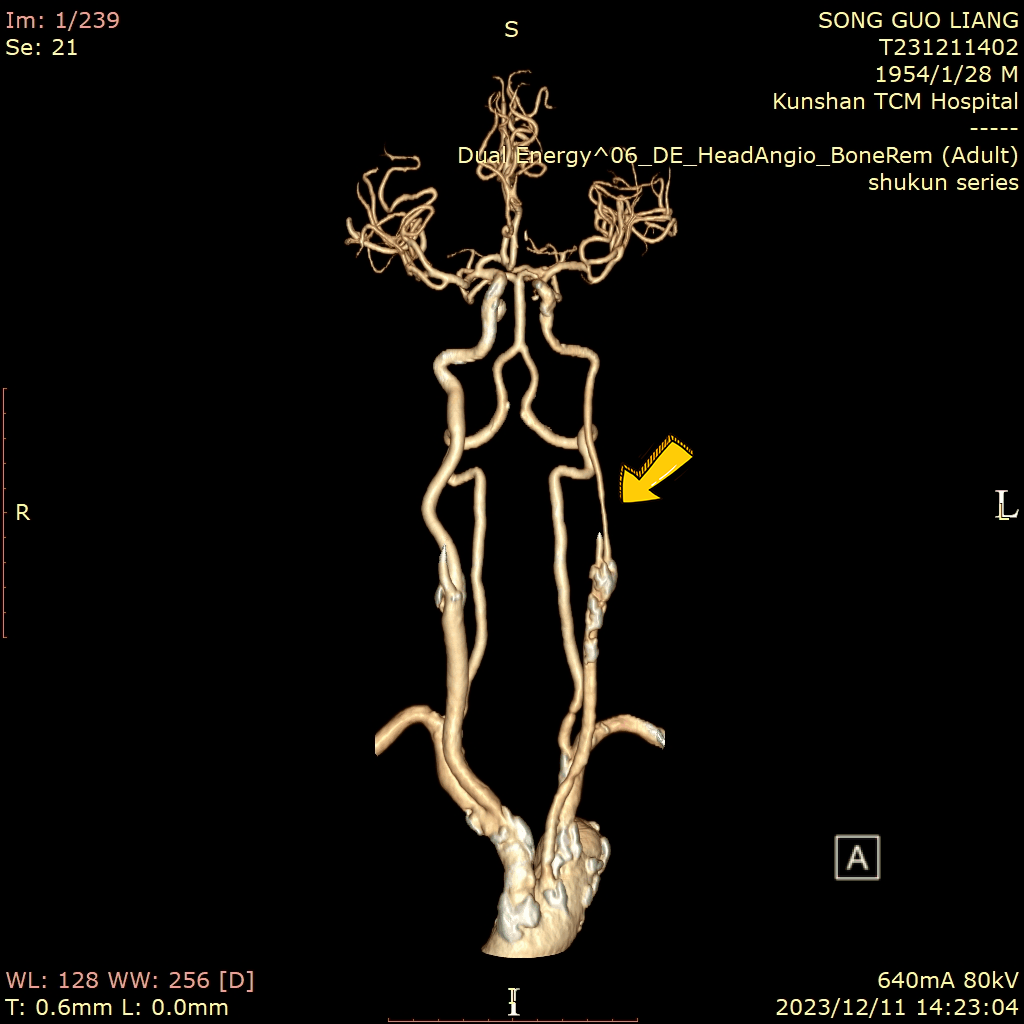

▲术前CTA检查见患者主动脉弓、颈动脉多处粥样硬化斑块,左颈总动脉分叉处血管重度狭窄